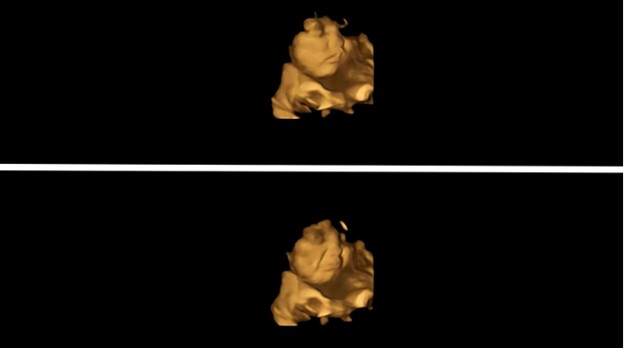

Para peneliti di Universitas Durham mengambil ultrasound 4D dari 100 wanita hamil pada minggu ke-32 dan 36, 20 menit setelah mengonsumsi tablet yang diisi dengan wortel atau bubuk kale.

Para peneliti menemukan, janin yang ibunya telah meminum tablet wortel tampak membuat ‘wajah tersenyum’ segera setelah itu. Tetapi pemindaian terhadap wanita yang mengonsumsi tablet kale menunjukkan bayi mereka membuat ‘wajah menangis’.

Penelitian yang diterbitkan dalam jurnal Psychological Science ini adalah yang pertama di dunia yang melihat bagaimana bayi bereaksi terhadap rasa dan penciuman sebelum mereka dilahirkan.

“Studi kami adalah yang pertama melihat reaksi ini sebelum kelahiran.Sungguh menakjubkan melihat reaksi bayi yang belum lahir terhadap rasa kangkung atau wortel selama pemindaian dan berbagi momen itu dengan orang tua mereka.”